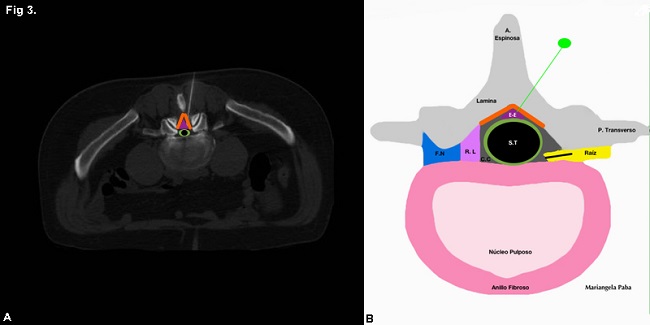

En total se estudiaron 46 pacientes, 34 mujeres (73,9%) y 12 hombres (26%) con una edad media de 67 años +/- 11,7 años (rango 33 a 89 años). En 27 (58%) de ellos se realizó bloqueo epidural (►Fig. 3) y en 19 (41%) bloqueo radicular (►Fig. 4) (►Gráfico 1).

Se utilizó iodopovidona para realizar la asepsia y se aplicó anestesia local con lidocaína al 2% para disminuir las molestias causadas por el procedimiento. Se introdujo una aguja espinal 21 G hasta el lugar afectado fuera radicular o epidural(►Fig. 1). Una forma de asegurar que se alcanzó la zona indicada en el caso de los bloqueos radiculares fue la reproducción del dolor referido por el paciente durante el interrogatorio, lo que se interpretó como contactando en el nervio comprometido (►Fig. 2). En bloqueos epidurales previo a la aplicación del medicamento, se inyectó 1 cm3 de aire para confirmar que la aguja se encontraba en el espacio correcto. En todos los casos se inyectó una solución compuesta de 30 mg de triamcinolona y 1,5 mg de clorhidrato de bupivacaina.